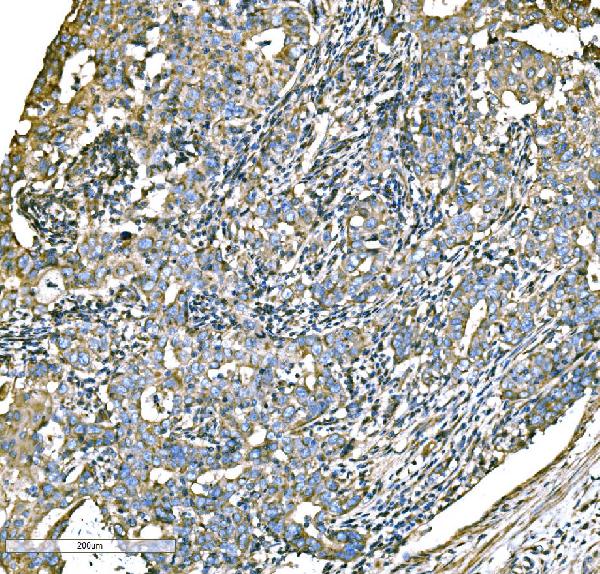

IHC (Immunohistochemisry)

(Figure 3. IHC analysis of ATG16L1 using anti-ATG16L1 antibody (AAA126035).ATG16L1 was detected in a paraffin-embedded section of human lung cancer tissue. Heat mediated antigen retrieval was performed in EDTA buffer (pH 8.0, epitope retrieval solution). The tissue section was blocked with 10% goat serum. The tissue section was then incubated with 2 ug/ml rabbit anti-ATG16L1 Antibody (AAA126035) overnight at 4 degree C. Biotinylated goat anti-rabbit IgG was used as secondary antibody and incubated for 30 minutes at 37 degree C. The tissue section was developed using Strepavidin-Biotin-Complex (SABC) with DAB as the chromogen.)